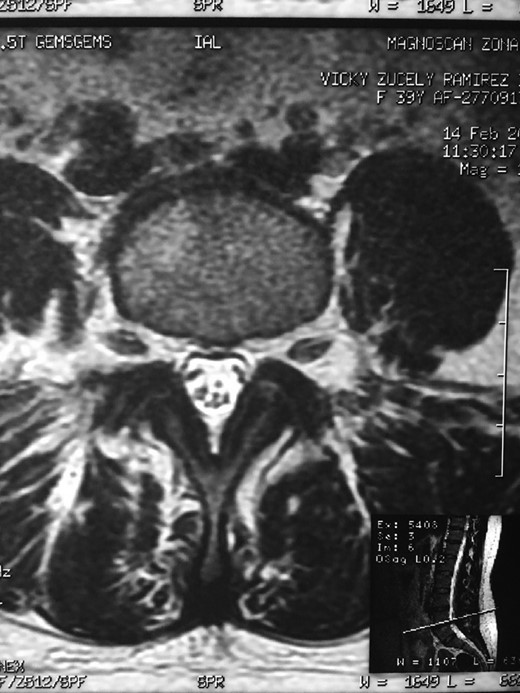

Showing the protective effect of the limitation of the motion in the distal disc to the anomaly.

The partial fusion at the lower part of the lumbosacral transition produces important alterations in normal biomechanics at the levels immediately above and below the LSTV. Changes such as hypermobility and abnormal torque moments are present at the level above the LSTV, predisposing it to early degeneration (early disc pathology and facet joint degenerative disease). Restricted movement below the LSTV produces a protective effect against degeneration of disc and facets and is related to changes (facets are smaller and coronally oriented) in the dimensions of the lower level facet joints [7]. These alterations can be verified in the adjacent levels of the LSTV in our patient.